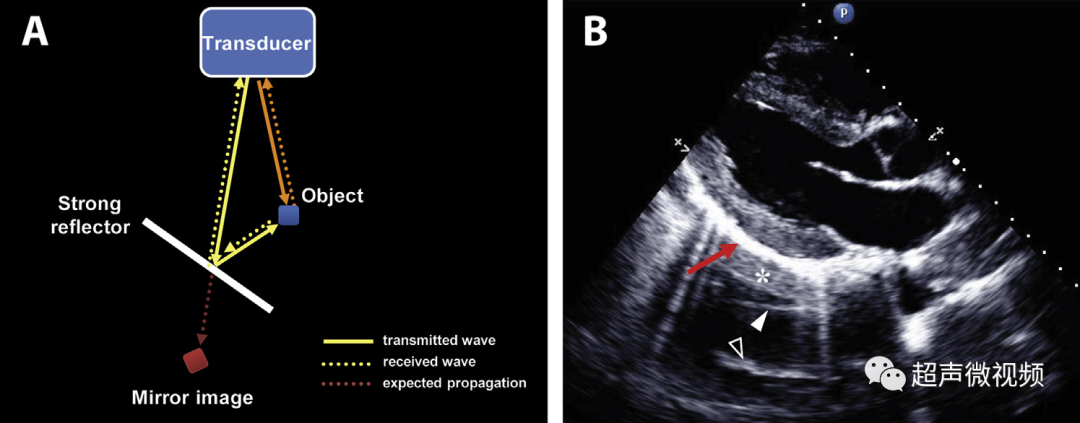

3、镜像伪影

镜面伪影通常出现在强反射表面之下,就像镜子对光的作用一样,在镜子后面产生镜子前真实结构的声像图;镜像的图像与镜像的方向相反,就像真实的结构一样。

最常见的强反射(镜面反射)导致镜像伪影的是肺。

图3 镜像伪影的理论成因(视频4)。(B)胸骨旁长轴图像显示心包-肺界面下方的镜像伪影(红色箭头)(视频5)。请注意后部心肌组织(星号)、后部二尖瓣叶(实心箭头)和前部二尖瓣叶(空心箭头)的镜像。由于强反射肺界面,心包下的彗尾反射也可以观察到。